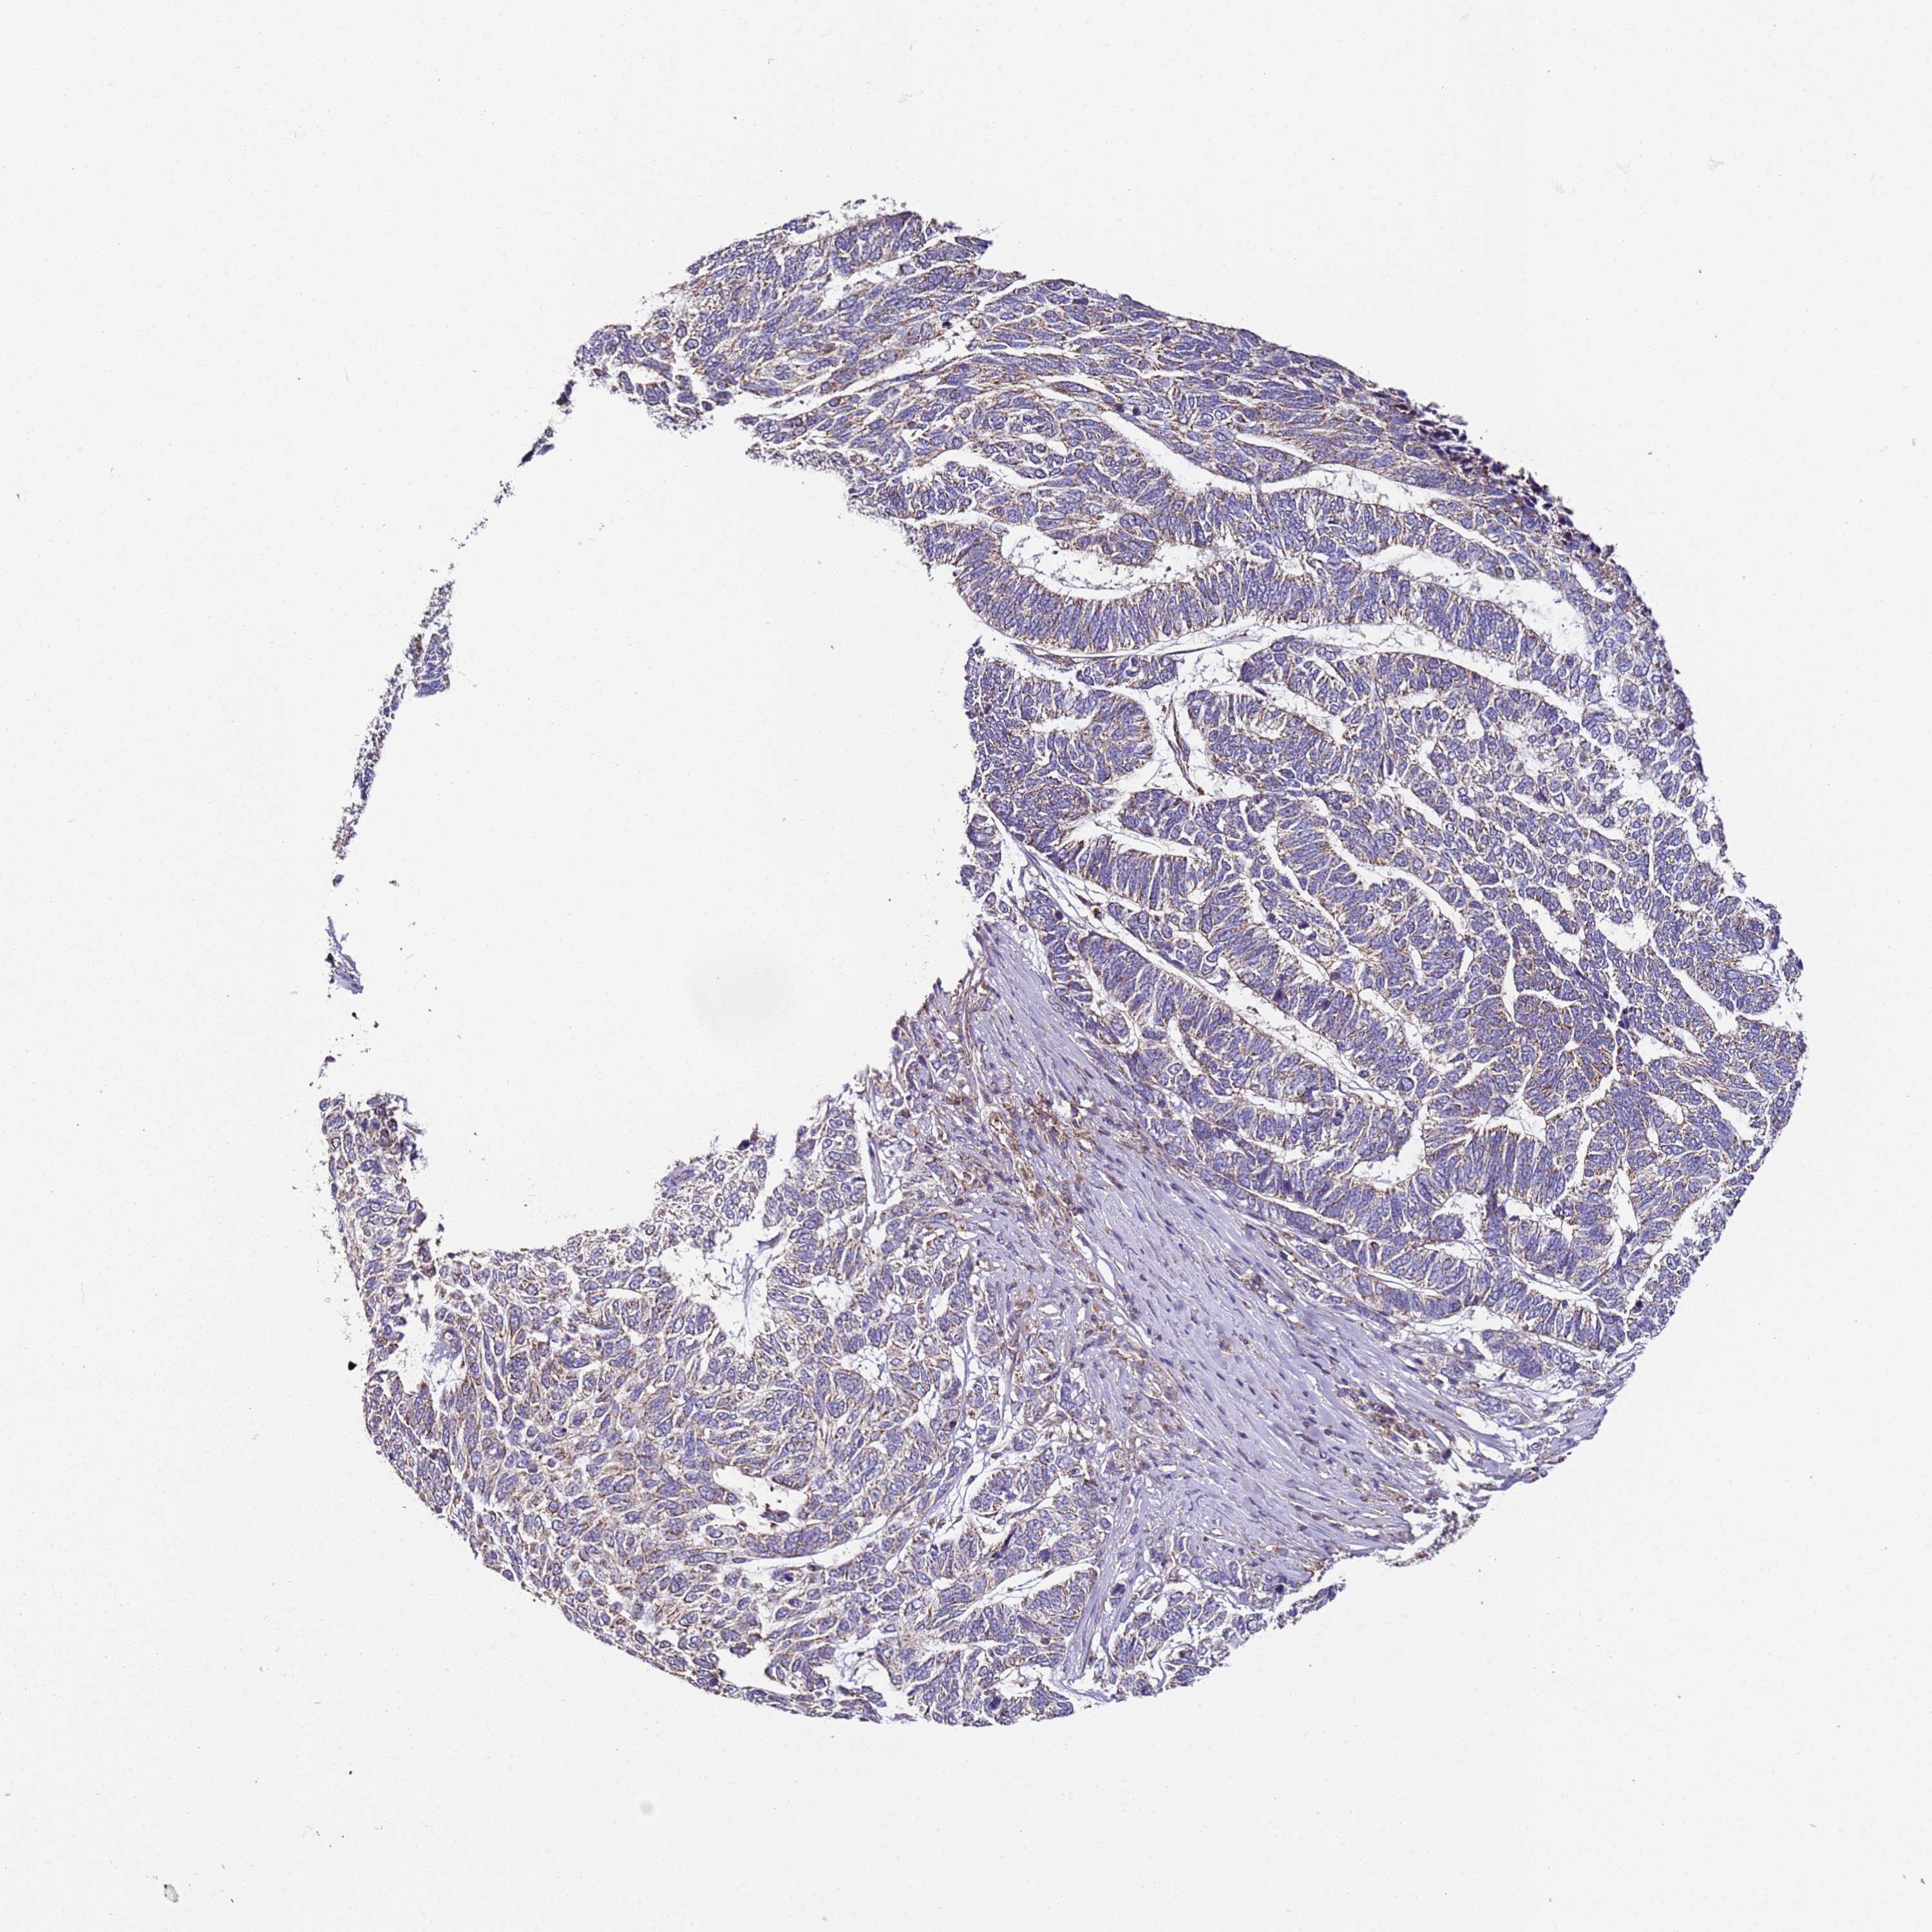

SKIN CANCER - Protein expressioni

A mouse-over function shows sample information and annotation data. Click on an image to view it in a full screen mode. Samples can be filtered based on level of antibody staining by selecting one or several of the following categories: high, medium, low and not detected. The assay and annotation is described here.

Each image is clickable and will lead to virtual microscopy that enables deeper exploration of all samples and also displays staining intensity scores, fraction scores and subcellular localization as well as patient and tissue information for each sample.

Antibody HPA046795

Staining

High

Intensity

Strong

Quantity

>75%

Location

Nuclear

Basal cell carcinoma